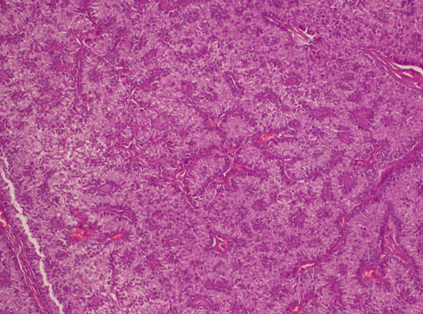

Five years later, she presented with abdominal pain. Computed tomography scan shows a 75 mm right adnexal mass evoking a cystic recurrence (Figure 2). The serum rate of anti-müllerian hormone (AMH) was elevated and measured 325 ng/ml. CA-125 rates were less than 35 UI/ml. In order to investigate PJS, a colonoscopy was performed and showed recto-colic polyposis. Mammogram showed benign cystic lesion of the breast. Papa smear did not show any abnormal cells. Radical surgery was recommended but the patient refused because of her will of childbearing. Laparoscopic exploration found a right adnexal cystic mass (Figure 3), with no evidence of ascites or peritoneal carcinosis. We underwent a cystectomy; leaving an ovarian tissue. The histologic findings showed circumscribed columnar epithelial nests composed of ring shaped tubules, which are encircled by hyalinized basement membrane-like material and concluded for a recurrent SCTAT. No mitotic count was reported (Figure 4) and (Figure 5). One month after surgery, hormonal rates were measured after ovarian stimulation and did not show hormonal activity. Fertility preservation attempt was a failure and the patient is proposed for a complementary surgery.

Figure 4: Sex cord stromal tumor with annular tubules of the ovary (H&E stain, x100).